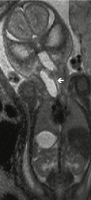

Pränataldiagnostik-Therapie

Abbildung 3: Fetales MRT branchiogene Zyste.

Keywords: branchiogene ZysteMRTPränataldiagnostikSpeculum